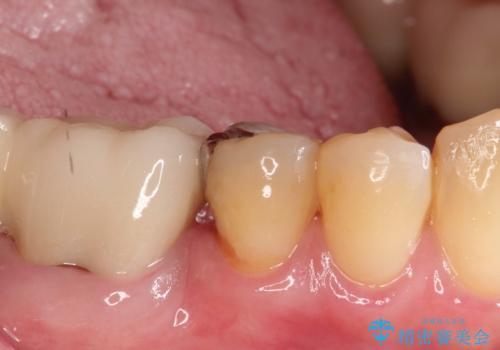

【PGAインレー】深い位置の二次カリエス

- 定期検診にて虫歯を発見したため、PGAインレーにて治療を行いました。

PGAインレーは金と白金を多く含み、精度高い修復が可能です。